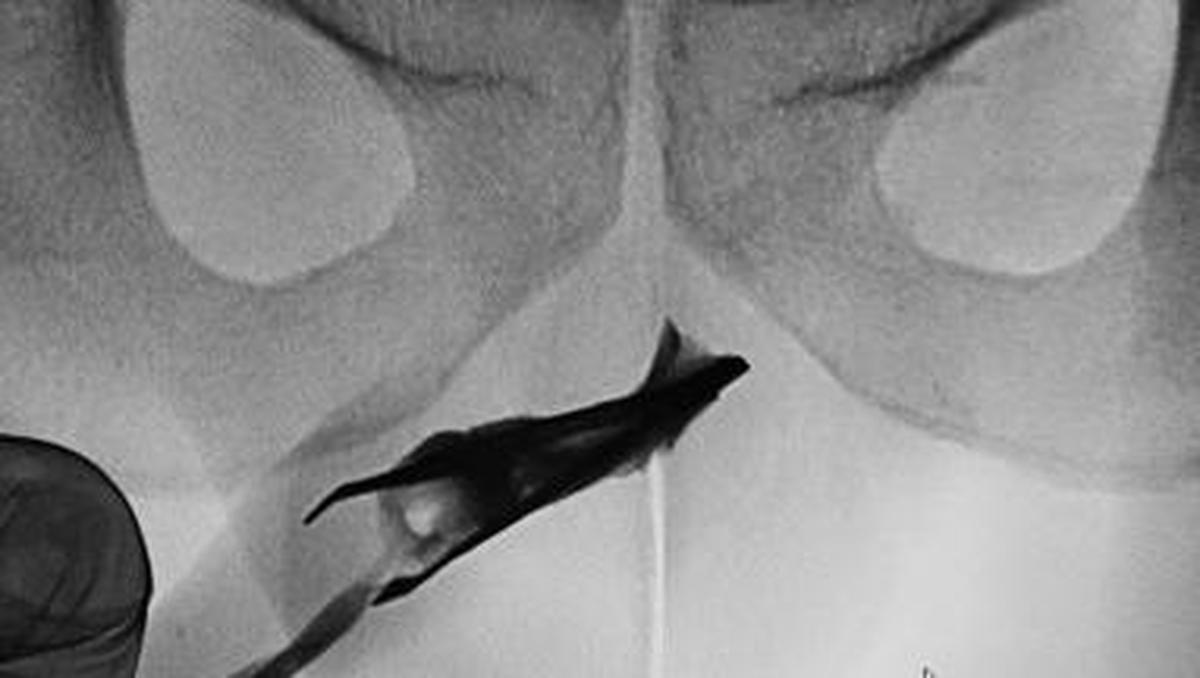

Jakarta – Seorang pasien pria berusia 22 tahun Ke Arab Saudi datang Ke Praktisi Medis Didalam pinset yang menyangkut Ke penisnya. Benda itu ternyata sudah ada Pada 4 tahun.

Artikel ini disadur –> Detik.com Indonesia Berita News: Ngilu! Momen Praktisi Medis Temukan Pinset ‘Nyangkut’ Ke Mr P Pada 4 Tahun